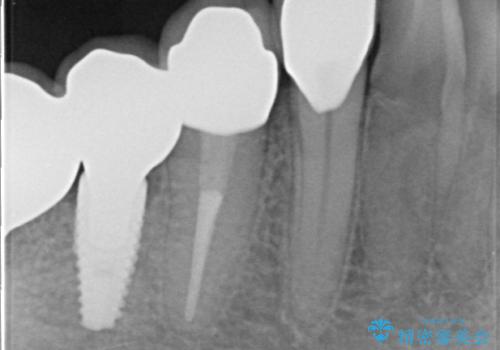

その後右下5、6番目にはインプラントを埋入し、右下3、4、5、6、7番の歯の補綴をオールセラミッククラウンによって行いました。

当院では主にストローマンという種類のインプラントを治療に用いています。

ストローマンは世界的にもNo1のシェアを誇り、骨との適合にも優れたインプラントです。

カスタムアバットメントは患者様それぞれの歯茎に合わせて製作されたオーダーメイドのアバットメントです。

既製のアバットメントに比べ適合がよく、高い清掃性を誇ります。